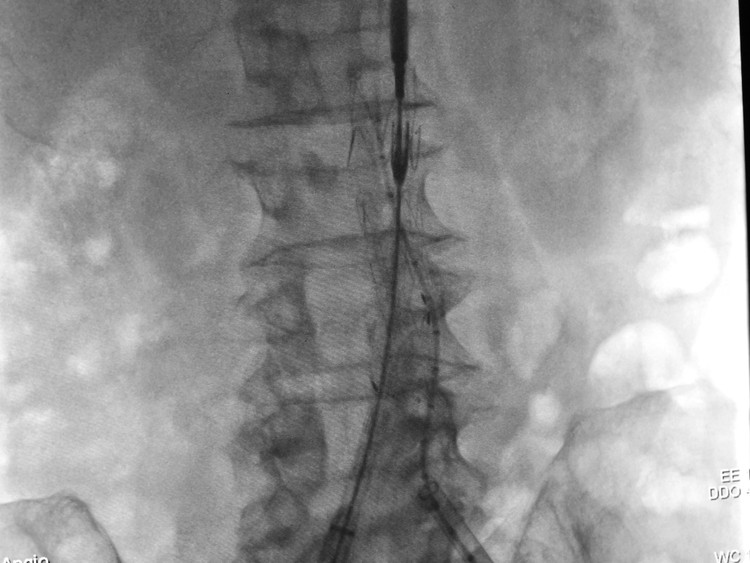

![]() |

| Hình ảnh stent graft với vai trò như một màng bọc vững chắc, giúp gia cố đoạn mạch tổn thương |